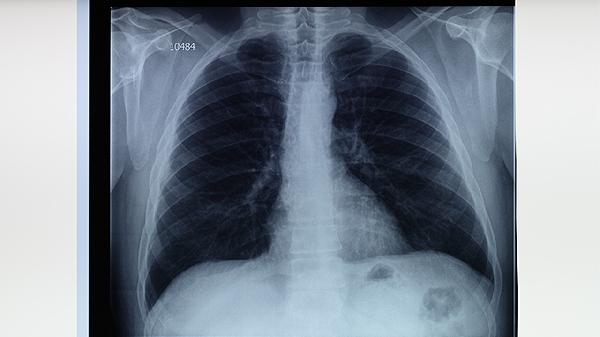

为避免传染,患者应佩戴口罩,减少与他人近距离接触。家庭成员应保持室内通风,定期消毒,避免共用个人物品。对于密切接触者,建议进行结核菌素试验或胸部X光检查,以便早期发现感染。